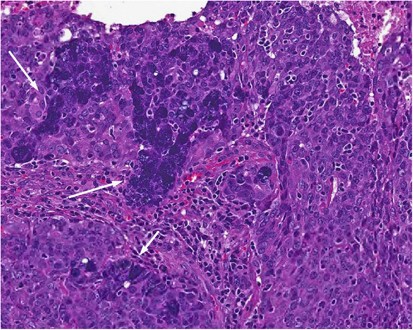

The differential diagnoses for basaloid salivary gland tumors with HGT includes salivary duct carcinoma, metastatic basaloid, and non-keratinizing squamous cell carcinoma (SCC), and non-salivary non-epithelial lesions. Salivary duct carcinoma may resemble any given basaloid tumor with HGT, as it is a pleomorphic adenocarcinoma that often shows necrosis and desmoplasia. The fundamental difference is that salivary duct carcinoma is an apocrine tumor and is thus ‘pink’ rather than blue. In addition, given this apocrine phenotype, it is characteristically androgen receptor (AR) positive. Most AR-negative tumors labeled as salivary duct carcinoma actually represent HGT of other entities, such as those noted above.38 Basaloid as well as non-keratinizing SCC can resemble salivary gland tumors ranging from ACC to BCAC. At minor salivary sites, primary basaloid or non-keratinizing SCC enters the differential diagnosis, while in parotid, metastasis enters the differential diagnosis. At primary sites, a surface or in situ component is a critical distinguishing factor since a primary salivary gland tumor is not expected to show this. When a metastasis is being considered, clinical history and immunohistochemical workup may be required. Notably non-keratinizing SCC metastases may masquerade as basaloid tumors (Figure 9). Rarely neuroendocrine carcinomas (metastases and rare primaries), as well as sarcomas (desmoplastic small round cell tumor, adamantinoma-like Ewing sarcoma, and biphasic synovial sarcoma) may enter the differential diagnosis.39 These are not usually intuitive initial diagnostic considerations, but warrant consideration if the typically salivary type entities are excluded, and the immunophenotype is not as expected.

An HPV-related SCC of oropharynx metastasizing to parotid and mimicking a basaloid tumor. The high-grade morphology can be similar to that of a primary salivary gland carcinoma with high-grade transformation. However, this tumor showed no areas of a conventional salivary type carcinoma, thus raising suspicion for a metastasis. Insets: left—p16 is diffusely strongly positive, and right—in situ hybridization for HPV-DNA shows punctate staining (arrows).